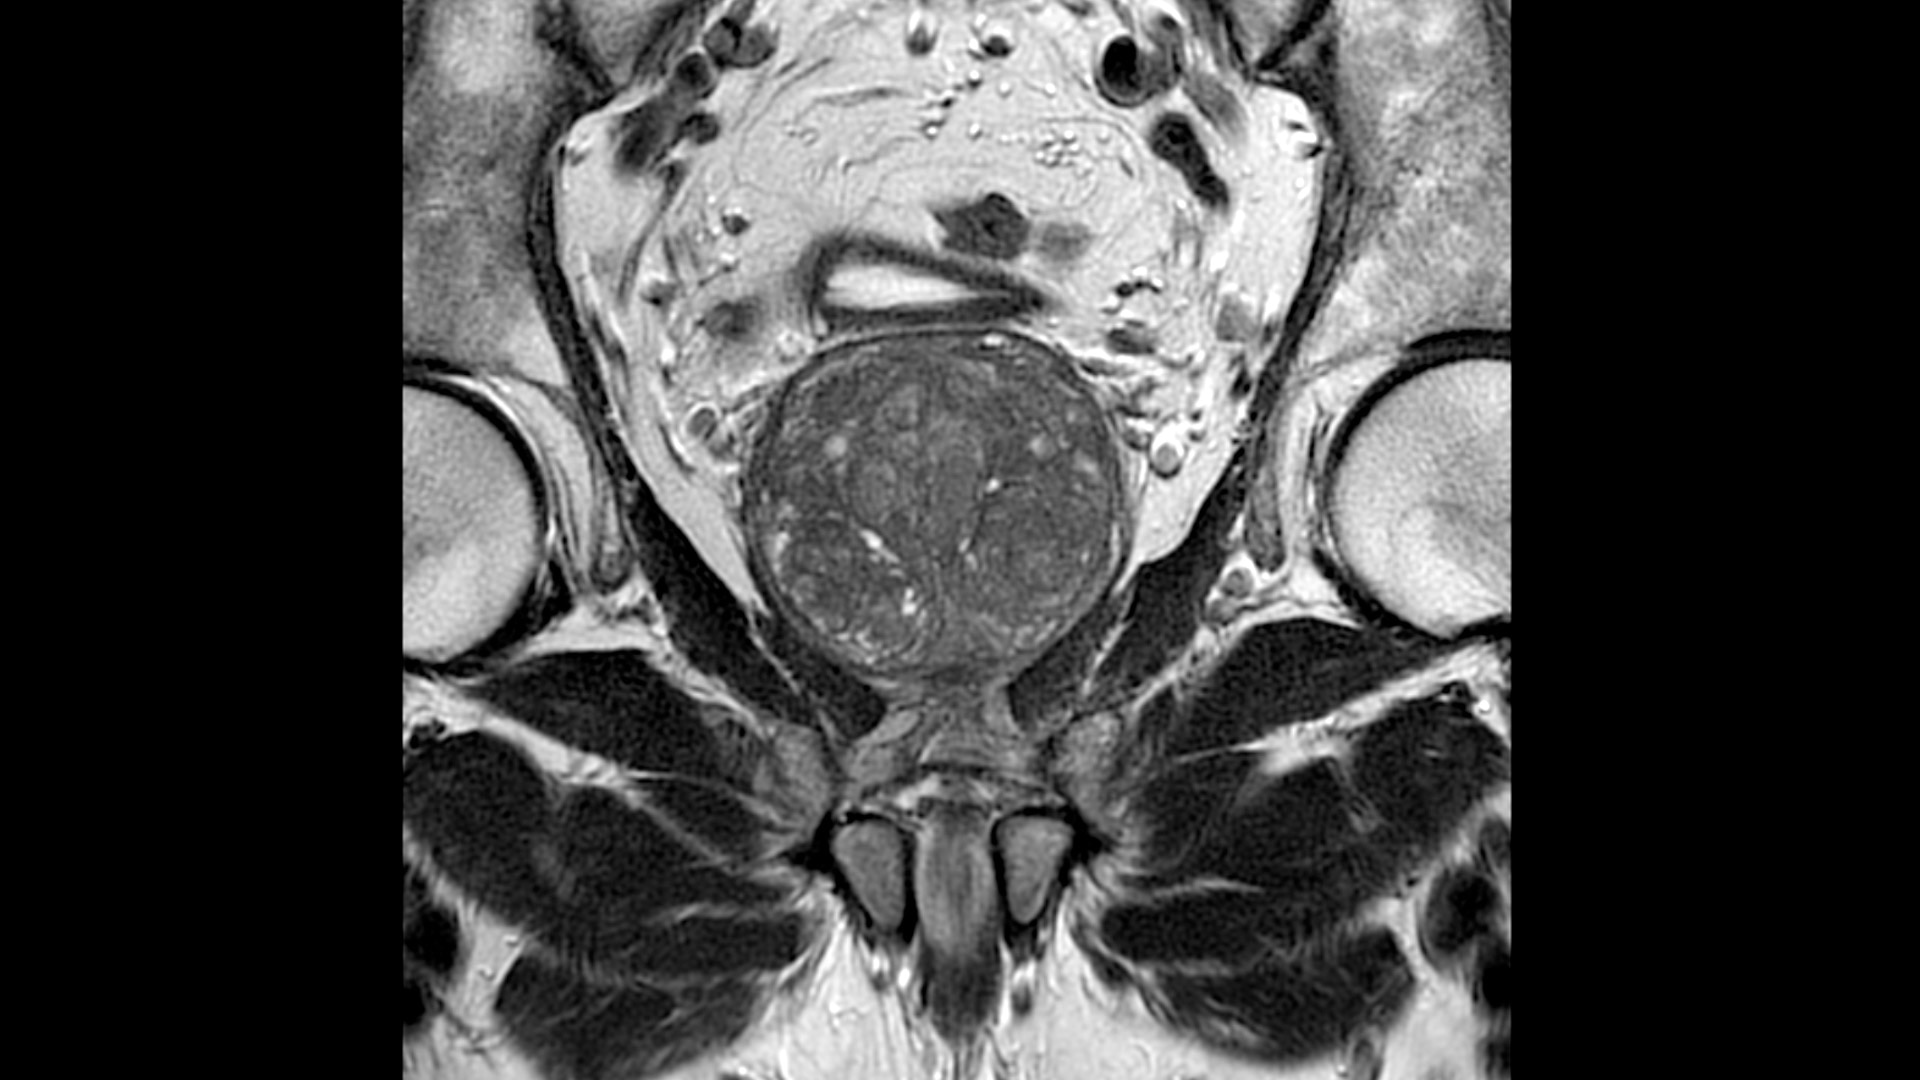

Improved patient comfort

Softer, lighter, and more flexible, our AIR™ Coils provide MRI patient comfort

Clinical excellence

Coil flexibility makes it easier to get closer to the patient, providing more coverage compared to other coils